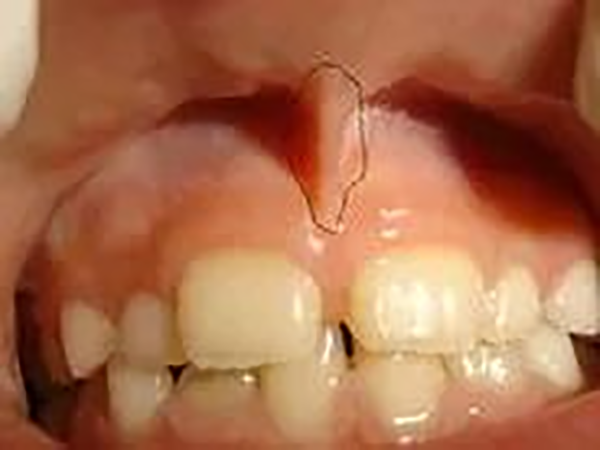

把宝宝的上唇翻开以后,会看到上唇正中与牙龈处有一根连接的像筋一样的东西,这就是上唇系带(图1)。宝宝摔倒面部受伤后,容易造成该系带断裂。口腔颌面部的血管丰富,所以受伤初期,上唇系带断裂的出血量相对较多,宝宝会看起来满嘴是血,比较骇人。这也是造成各位家长惊慌的主要原因。

图1 上唇系带的位置(图片来源于网络)